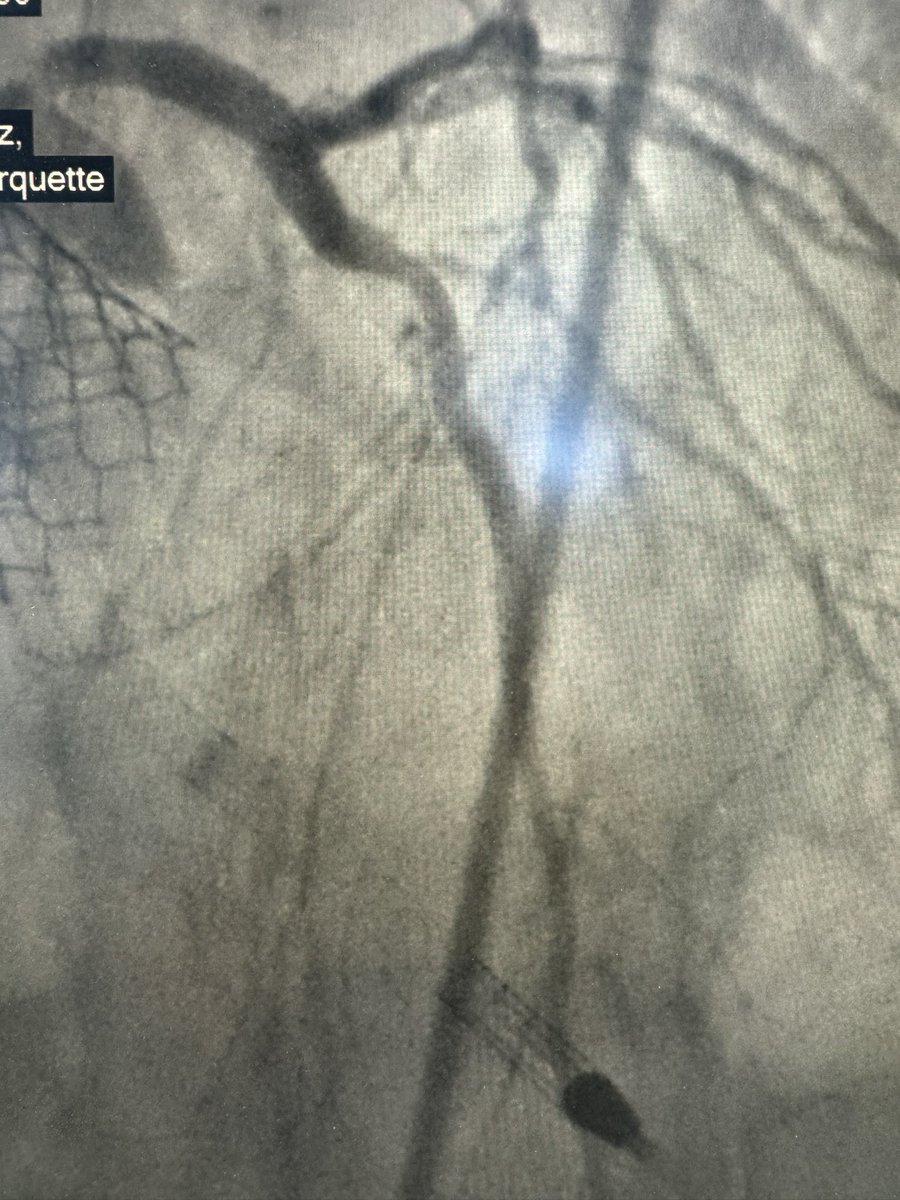

Prior tavr patient comes in 95% left main,hostile cfa’s. U/s guided left axillary and Perc ax impella . CSI to left main single stent to lad plus pots. PTA assisted dry closure with2 preclose w excellent hemostasis. @jcgeorgemd @jaygirimd @DrAmirKaki @JayMathewsMD